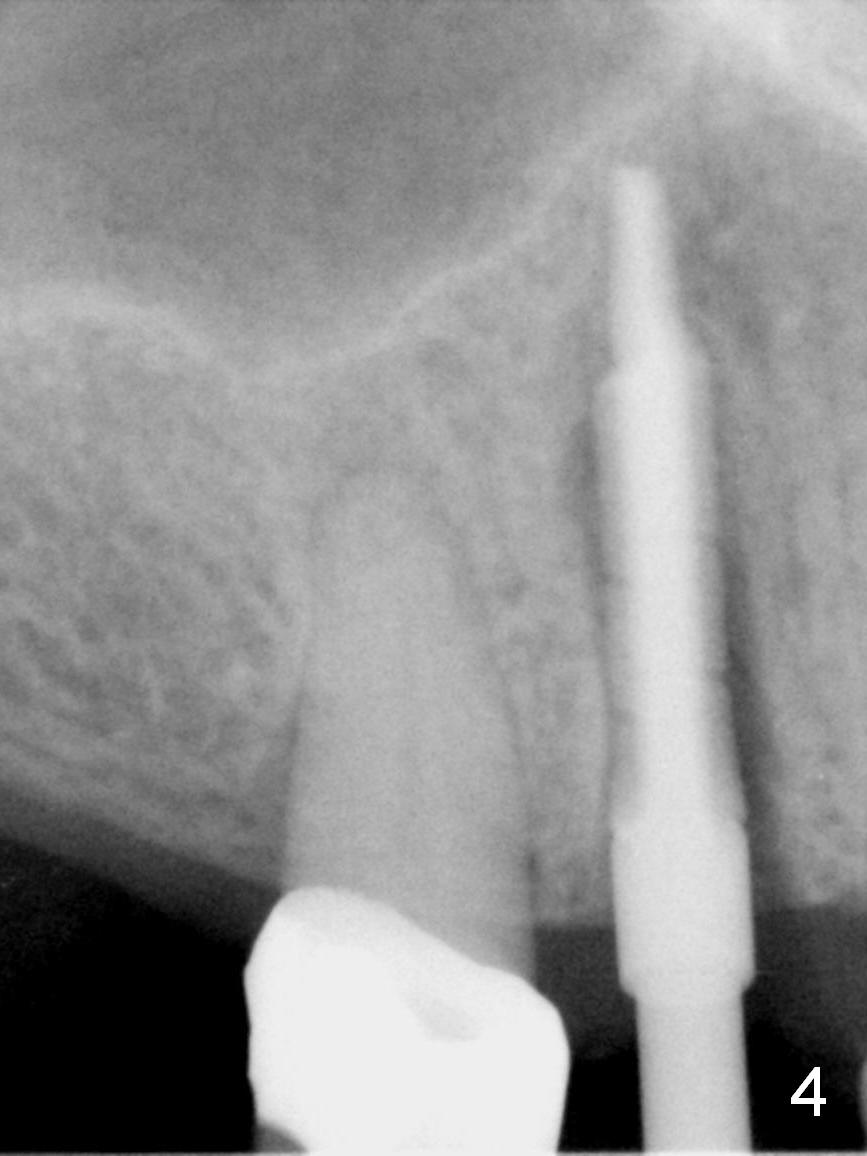

After long discussion, she agrees with extraction and immediate implant.  After the extraction, granulation tissue is removed.  There is buccal apical fenestration.  The socket is treated with Metronidazole.  The socket depth is 17 mm, while osteotomy depth is 20 mm (Fig.4).  A 4x20 mm tissue-level implant is placed with primary stability (Fig.5,6 I).  A short abutment (A) is placed immediately for an immediate provisional.  The buccal gap is filled with Osteogen plug.  There is no crestal bone loss 3 months postop (Fig.7).  The provisional stays in place with occlusal perforation.  The gingiva is healthy 5.5 months post cementation (Fig.8).